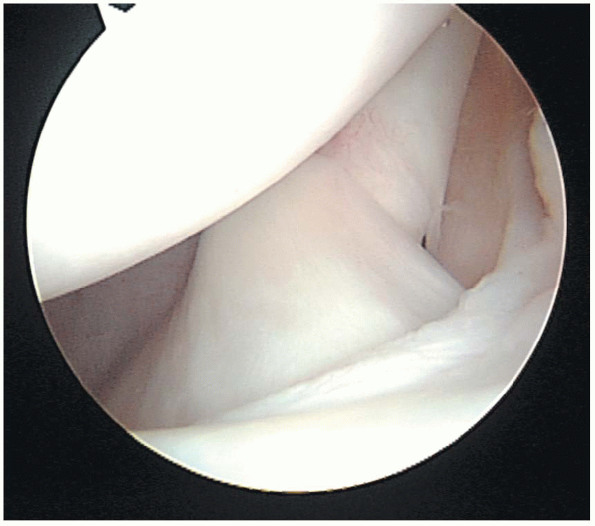

FIGURE 1-2.

The humeral head is typically round and covered with smooth articular cartilage. A normal “bare area” of bare bone is present between the edge of the articular surface and the insertion of the posterior capsule. This bare area should not be confused with a traumatic Hill Sachs lesion. A Hill Sachs lesion typically is found posterosuperiorly on the humeral head and has no vascular channels, whereas the bare area has normally appearing vascular channels. |

of the glenoid and the humeral head must be fully evaluated during

arthroscopy. The glenoid is an ovoid or pear-shaped cavity that is

approximately one fourth the size of the humeral head. Its surface is

covered by articular cartilage. However, there is a normal central area

with little or no cartilage present. At the anterior glenoid margin a

notch or indentation is present, which should not be mistaken for an

anterior lip or Bankart lesion related to anterior instability. The

humeral head is typically round and covered with smooth articular

cartilage. Posteriorly, it has a normal “bare area” or sulcus, which is

a region of bare bone present between the edge of the articular surface

and the insertion of the posterior

capsule (Fig. 1-2).

This bare area should not be confused with a Hill Sachs lesion, a

posterior humeral head compression fracture associated with anterior

dislocations of the glenohumeral joint. A Hill Sachs lesion typically

is found posterosuperiorly on the humeral head and has no vascular

channels, whereas the bare area has normally appearing vascular

channels. A reverse Hill Sachs lesion, associated with posterior

dislocations is an extremely rare pathologic finding during

arthroscopy. It appears as a wedge-shaped defect toward the lateral

insertion of the subscapularis tendon on the lesser tuberosity. In all